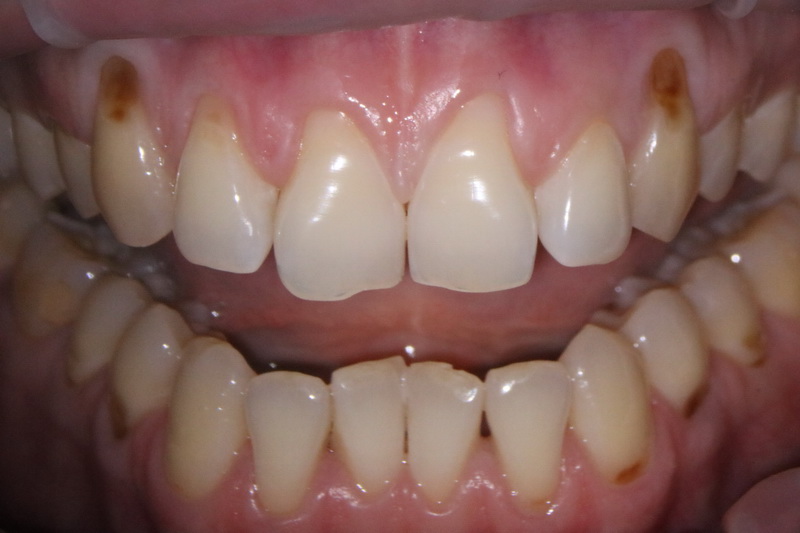

Клиноподібний дефект – це некаріозний дефект емалі, що розташовується на вестибулярній поверхні зуба в пришийковій зоні, тобто зі сторони губ та щік біля ясен.

Клиноподібний дефект сам по собі зникнути не може і з часом це призводить до повного стирання твердих тканин в пришийковій ділянці і як наслідок виникають переломи або сколи зубів.

Симптоматично можна зняти гіперчутливість цих зубів, відреставрувати ці дефекти за допомогою композитної чи керамічної реставрації. А щоб подіяти на причину ми маємо виправити вади прикусу, що призводять до перевантаження зубів або навчити пацієнта правильним навичкам гігієни.